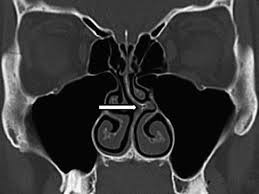

Le scanner : cet examen radiologique est souvent demandé dans un but diagnostic en précisant les structures nasales mais surtout en visualisant l’intérieur des sinus (qui ne sont pas visualisés par l’examen endoscopique), mais surtout dans le cas du bilan préopératoire quand un traitement chirurgical est envisagé.

Ce traitement est indiqué quand les facteurs anatomiques d’obstruction nasale ou de confinement sinusien sont présents à l’examen clinique et au scanner.

Le diagnostic repose sur l’interrogatoire, sur l’examen clinique et sur quelques examens complémentaires clés.

Le Scanner est parfois prescrit, surtout en cas de pathologie sinusienne associée ou de pathologie tumorale